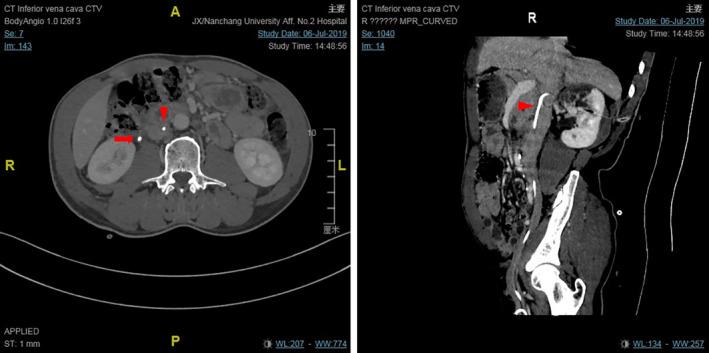

Endovascular removal of a misplaced ureteral stent in the vena cava: a complication of ultrasound-guided percutaneous nephrolithotomy.

Intravascular migration of a double J stent into the inferior vena cava is an uncommon complication. Active prevention, timely diagnosis, and early intervention are crucial for this complication. Intravascular interventional therapy is relatively easy, less traumatic, and has a high success rate. It can be used to select patients for intravascular ectopic DJS treatment.

https://cdn.ncbi.nlm.nih.gov/pmc/blobs/9005/7813050/73ee31270f54/CCR3-9-77-g001.jpg